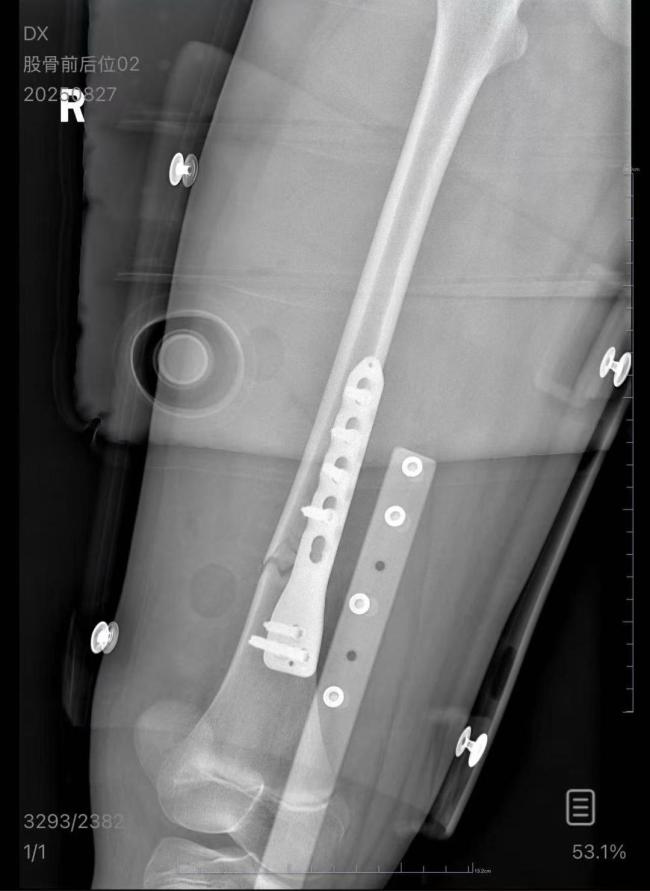

根据男乘客的说法,火车快到无锡站时,他准备下车,从上铺下来后想起还有一副眼镜忘在了铺位上,于是又爬回床铺。这时车晃动了一下,他的手没抓稳,跌下来砸到了女孩。医院诊断结果显示,朱女士的女儿右股骨骨折,需要住院进一步治疗。